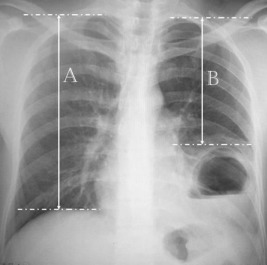

Using PA pulmonary radiography, the distance between the peak of the intactus hemidiaphragm and apex point of the ipsilateral hemithorax was measured with this new method. (1) Similarly, the distance between the peak of the eventrated hemidiaphragm and the apex point of ipsilateral hemithorax was measured. (2) The ratio of B/A and eventration level was calculated as a percentage ( Figure 1).

Preoperative chest X-ray.

Example:

A = 25 cm, B = 20 cm